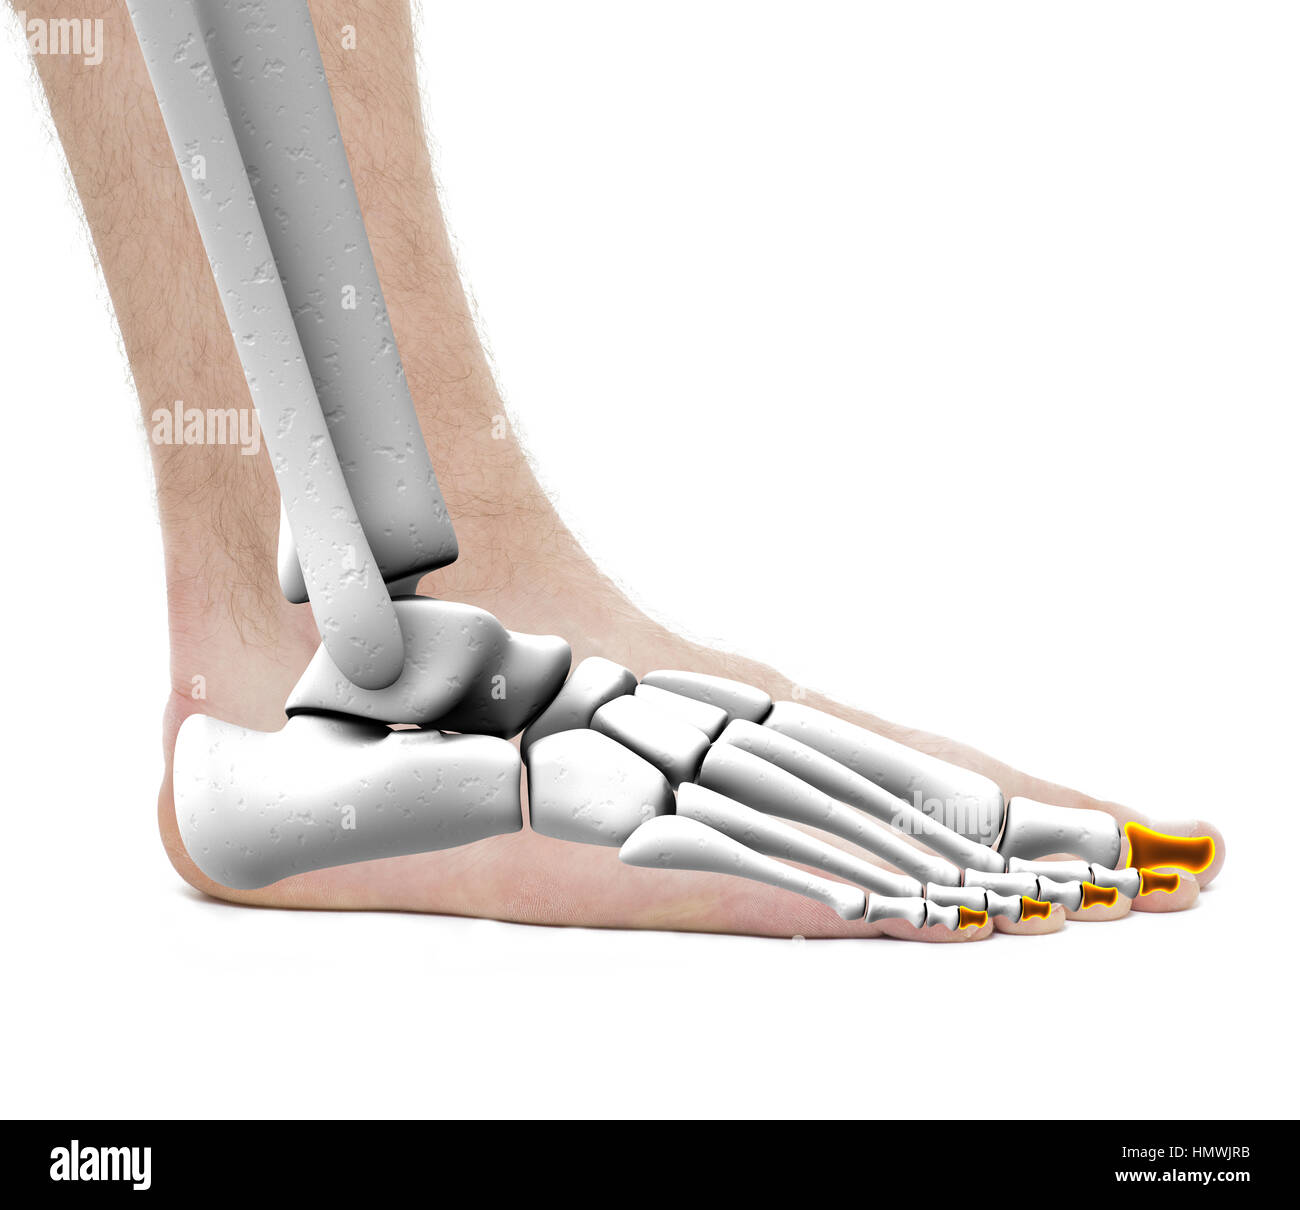

RF2R3WKY1–Illustration médicale des principales parties des os du pied en vue latérale, avec annotations.